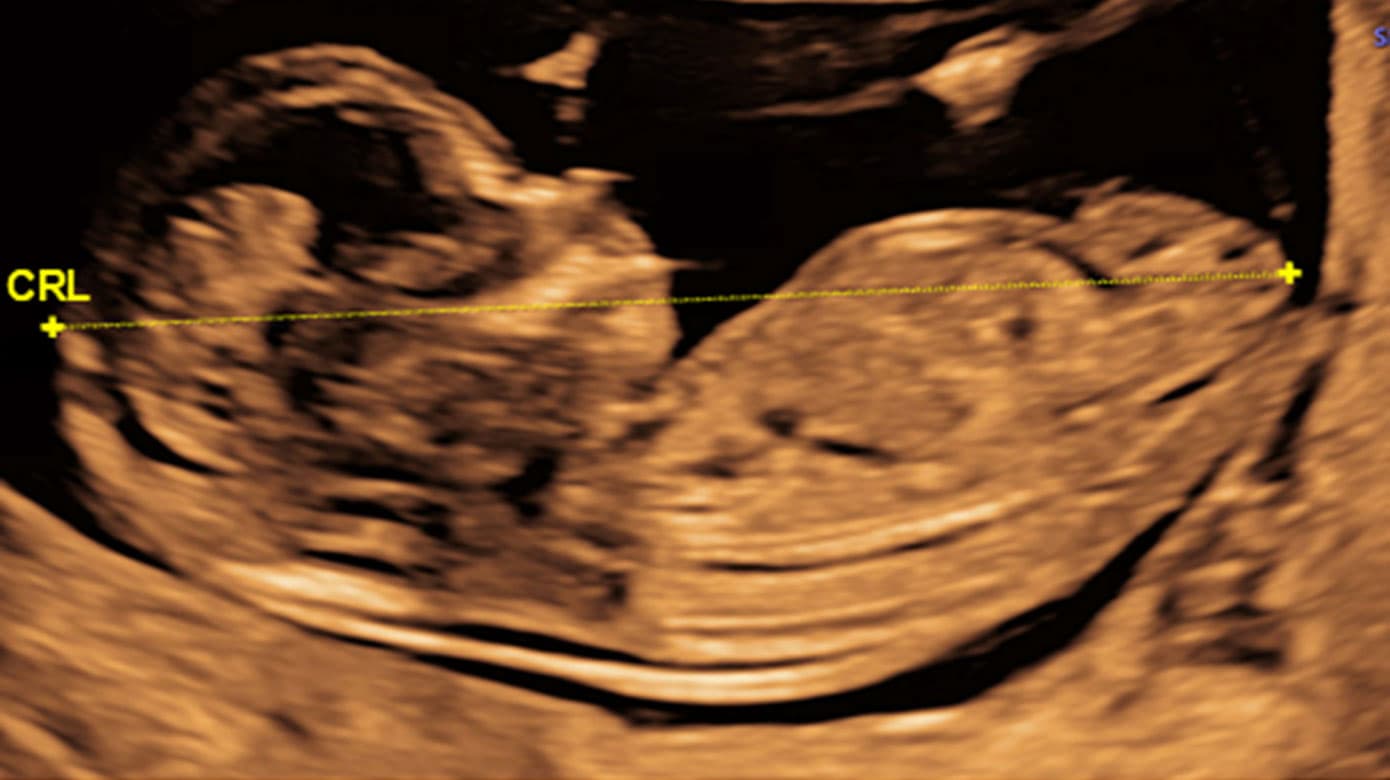

1. trimester-screeningsundersøgelsen er et tilbud til alle gravide, som den gravide informeres om hos egen læge i forbindelse med første svangreundersøgelse. Undersøgelsen foretages ved GA 11-14 uger af en sonograf, der er certificeret i nakkefold (NF)-skanning. Ved skanningen undersøges for fosterhjerteaktivitet, antal fostre samt for choriositet ved flerfoldsgraviditet. GA bestemmes ved måling af crown rump length (CRL) (Figur 1 A). Herudover måles NF-tykkelse (Figur 1 B), hvis den gravide ønsker sandsynlighedsvurdering for trisomi 21, trisomi 18 og trisomi 13. Fosteret undersøges desuden for større misdannelser, herunder større CNS-misdannelser (f.eks. anencefali), svære hjertemisdannelser, bugvægsdefekter og større skeletmisdannelser (f.eks. manglende ekstremiteter). Sandsynlighedsvurderingen beregnes ud fra den gravides alder, NF-tykkelse og biokemiske markører målt ved en blodprøve. Blodprøven (doubletesten) tages ved egen læge eller på hospital ved GA 8-14 uger. I blodprøven analyseres to proteiner, der begge produceres i placenta: pregnancy-associated-plasma-protein A (PAPP-A) og frit beta-humant choriongonadotropin (fβ-hCG). Den målte koncentration af begge markører omregnes til multiples of the median (MoM)-værdier, da de varierer betydeligt med GA, ligesom de justeres for diverse maternelle karakteristika, der vides at påvirke koncentrationen – bl.a. paritet, vægt, rygning, etnicitet og konceptionsmåde. Alle data samles i det føtalmedicinske softwareprogram Astraia, der udregner sandsynligheden for trisomi 21, 18 og 13. Hvis den gravide har en sandsynlighed for trisomi 21 på ≥ 1:300 og/eller trisomi 18 eller 13 på ≥ 1:150, tilbydes yderligere undersøgelse. Ligeledes tilbydes yderligere undersøgelse ved tilstedeværelse af et af følgende enkeltkriterier for atypiske kromosomfejl: alder ≥ 45 år, NF ≥ 3,5 mm, PAPP-A eller fβ-hCG ≤ 0,2 MoM, fβ-hCG ≥ 5 MoM, eller hvis der er påvist en misdannelse hos fosteret.